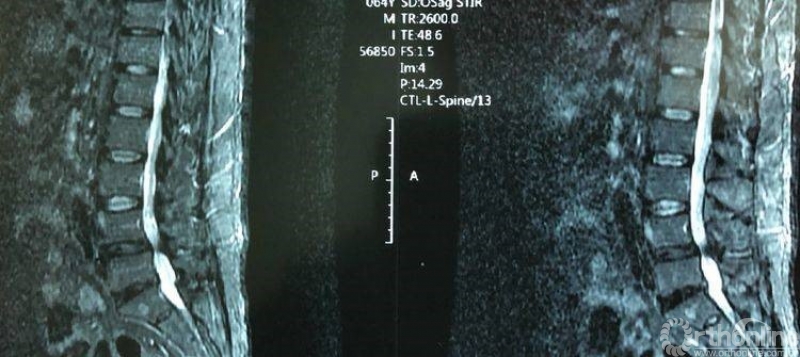

术前腰椎核磁共振矢状面